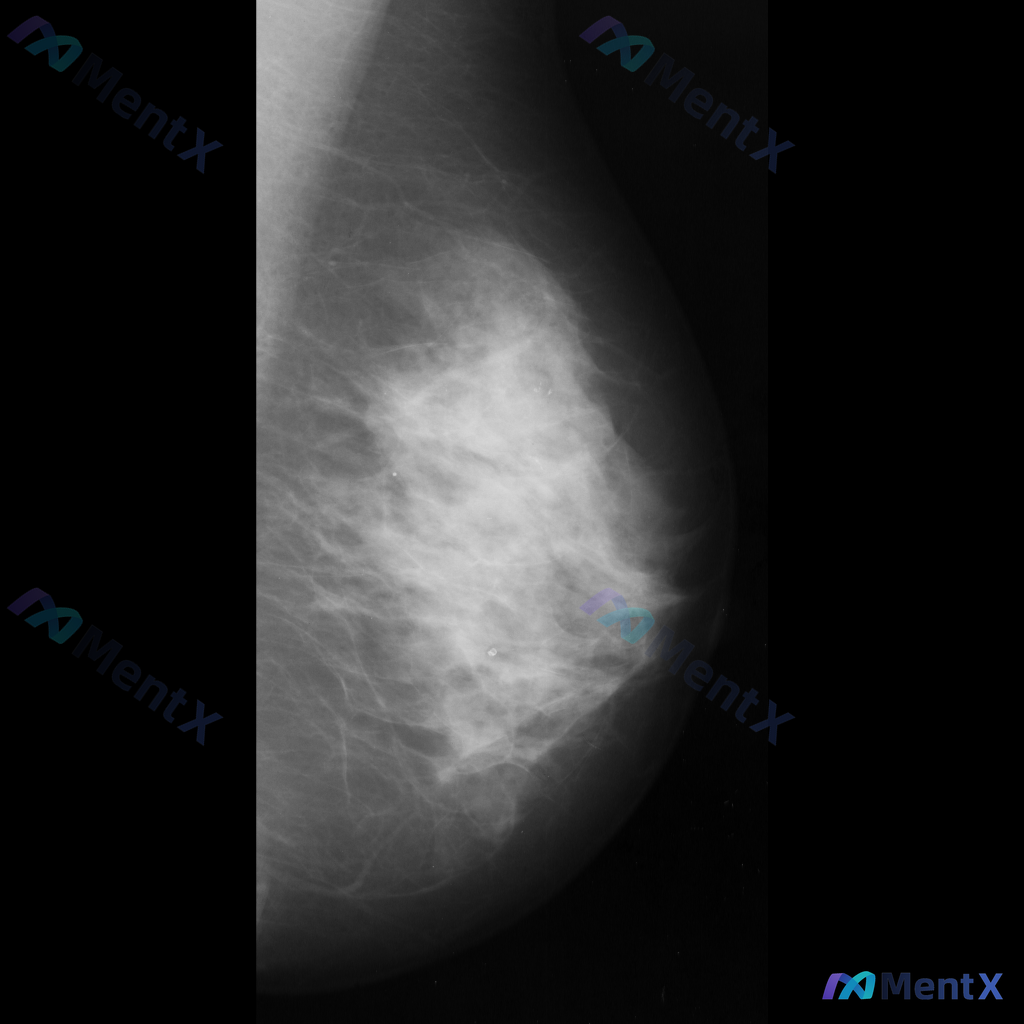

整理了一张乳腺钼靶影像的讨论资料,先和大家分享一下读片描述: 影像可见:不规则、高密度肿块/不对称致密影,伴有毛刺状边缘、结构扭曲和散在钙化。 目前考虑可能存在几种不同的异常方向,想先听听大家的第一反应——单看这组影像特征,你会先往哪种情况考虑? 也可以说说你最关注的是哪一点表现。

整理到一张单侧乳腺钼靶影像的读片资料,目前是单一体位图像,没有双侧对比。 影像表现整理 - 乳腺组织密度较高,属于多量腺体型或致密型背景 - 可见散在的钙化灶:图像中部偏下有数个点状或粗大钙化,形态不规则,但无典型恶性钙化的细小多形性、线样或分支状表现 - 乳腺下象限可见多个高密度圆形/卵圆形影,边...

整理到一张乳腺钼靶影像的读片资料,想和大家讨论一下读片思路: 影像里能看到的主要异常是乳腺内结构扭曲(正常导管小叶结构有集中、牵拉、不规则向中心汇聚的表现,但没有明确肿块),同时还有不对称致密影(局部组织密度增高,和周围或对侧分布不太一致)。另外,乳腺本身纤维腺体组织偏多,可能属于 BI-RADS...

整理到一份单侧乳腺钼靶的影像资料,想和大家讨论一下读片思路: 影像背景与征象 - 背景:不均匀致密型乳腺 - 主要异常: 1. 乳腺中央及中下部可见一片边界模糊的斑片状/不规则形密度增高区 2. 该密度增高区域内,似乎存在乳腺正常小梁结构的牵拉或紊乱 3. 中下部偏乳头方向,有一组较为集中的、形态不...

整理到一张乳腺钼靶影像的讨论资料,先把关键信息列出来,大家帮忙看看: - 影像类型:左乳内外斜位(MLO位)钼靶 - 背景:乳腺呈多量腺体型(致密型),腺体组织丰富 - 主要发现:左乳下象限可见局灶性不对称密度,伴有腺体结构轻度紊乱 - 其他:目前未见明确的异常钙化、导管增粗或皮肤异常 单看这张影像...